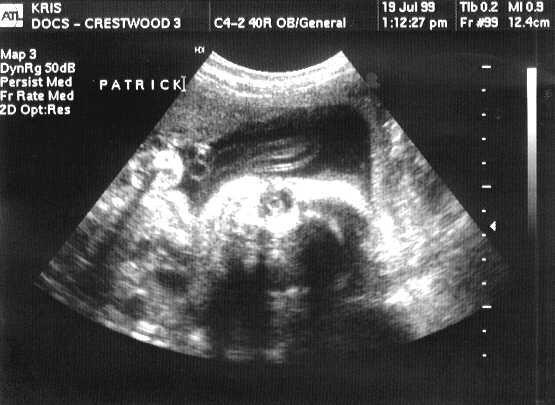

V-Twins Names

This is PATRICK JOSEPH.